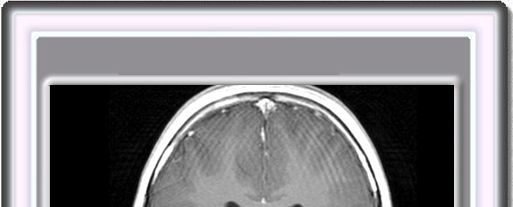

En un 50% de los casos, las lesiones subependimales y subcorticales van acompañadas de astrocitomas de células gigantes que se localizan frecuentemente en las proximidades del foramen de Monro, produciendo hidrocéfalo obstructivo.